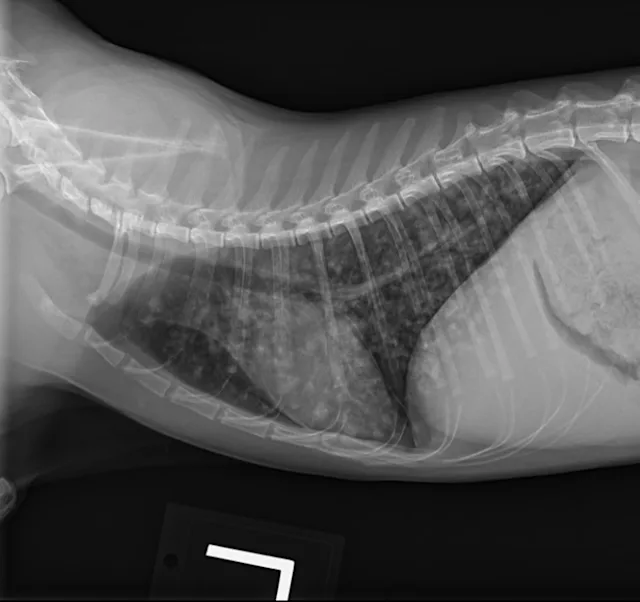

Butorphanol (0.2 mg/kg IV) was administered for sedation to obtain 3-view thoracic radiographs (left lateral, right lateral, ventrodorsal). Results revealed diffuse pulmonary nodular changes with an underlying bronchointerstitial pattern (Figure 1). Fungal pneumonia, parasitic pneumonia, neoplasia, and eosinophilic inflammatory disease were the most likely differentials for this pattern.

A

FIGURE 1 Left lateral (A), right lateral (B), and ventrodorsal (C) thoracic radiographs at the time of initial diagnosis. Diffuse pulmonary nodular changes with an underlying bronchointerstitial pattern can be seen.